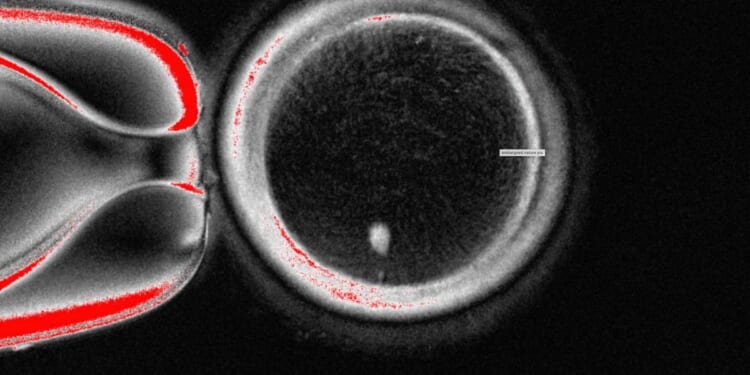

The OHSU team removed the nucleus from a human egg cell and replaced it with the nucleus from a human skin cell. But a skin cell contains two sets of chromosomes, and eggs and sperm are supposed to each contain only one set that combine during fertilization. The researchers therefore induced the egg-like cells to discard extra chromosomes, injected donated sperm and jump-started post-fertilization development.

About 9% lasted for six days in lab dishes, reaching the blastocyst stage of early embryo development, before the experiment was stopped.